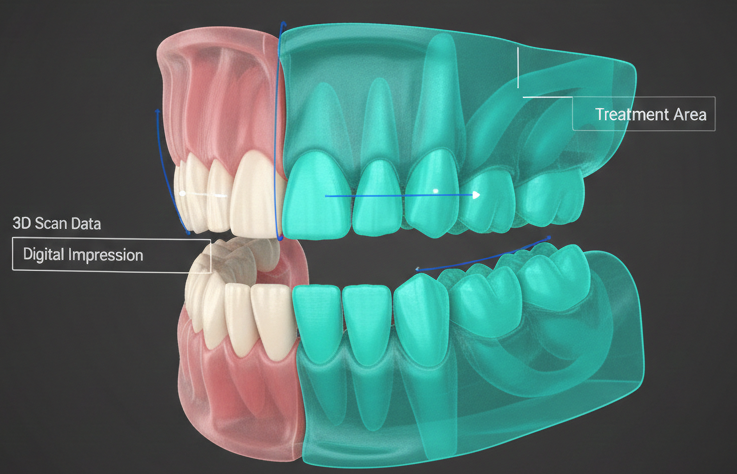

Für die Planung von Zahnersatz nutzen wir einen hochmodernen Intraoralscanner, der herkömmliche Abdruckmassen ersetzt und ein hochpräzises, digitales 3D-Abbild Ihres Gebisses erstellt.

Unser hochmoderner Intraoralscanner ersetzt den herkömmlichen Abdruck durch eine schmerzfreie, digitale 3D-Aufnahme Ihres Gebisses in Sekundenschnelle. Genießen Sie eine präzise Behandlungsplanung ohne Würgereiz und erleben Sie Ihr mögliches Behandlungsergebnis direkt als anschauliches Modell am Monitor.

Höchste Präzision und mehr Sicherheit garantiert die 3D-Implementation, bei der wir die optimale Positionierung der Implantate bereits vorab digital am Computer planen.

Dank hochmoderner 3D-Implantation planen wir Ihren Zahnersatz mit digitaler Präzision am Computer, noch bevor der eigentliche Eingriff beginnt. Diese Technologie bietet Ihnen maximale Sicherheit und eine minimalinvasive Behandlung, da die optimale Position der Implantate exakt auf Ihre individuelle Anatomie abgestimmt wird.